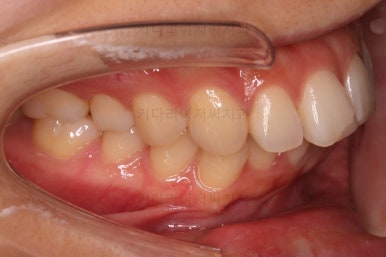

마찬가지로 부산연산동교정치과 초진 시 입안의 모습입니다.

아래 앞니도 삐뚤한 편이었고 아래 앞니가 불쑥 위로 올라와 있어서 이를 악 다물면 위아래 앞니가 많이 겹치는 "과개교합" 패턴이 나타나요.

윗니가 전반적으로 아랫니보다 앞에 나와 있어서 2급 부정교합에 윗니만 튀어나온 양상이고 이 때문에 윗니 앞니가 다치고 부러졌따가 떼운 흔적이 보이네요.